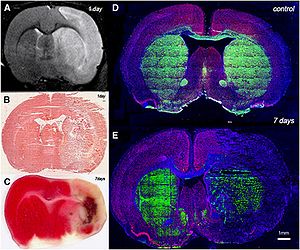

- 4.2 Comparison of Acute and Chronic Traumatic Brain Injury Using Semi-automatic Multimodal Segmentation of MR Volumes

- 4.3 3D Slicer